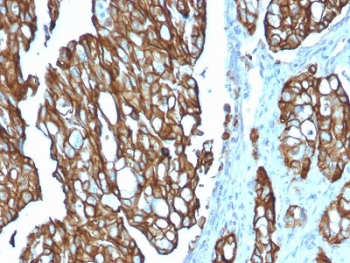

IHC testing of FFPE human pancreatic carcinoma with TROP2 antibody (clone TACSTD2/2151). Required HIER: boil tissue sections in pH 9 10mM Tris with 1mM EDTA for 10-20 min followed by cooling at RT for 20 min.